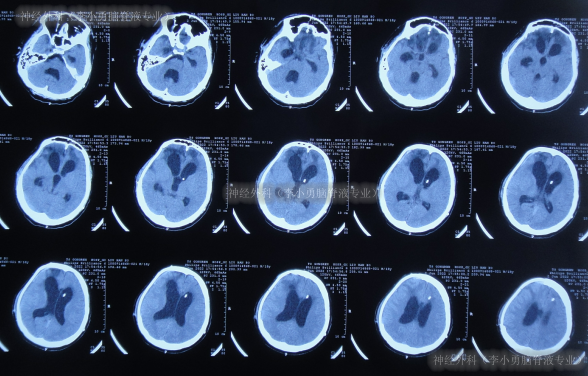

去骨瓣减压+血肿清除术后第2天即2022年2月3日,头颅CT示出血有增多(图-3)。

图-3:2022年2月3日头颅CT

术后3天即2022年2月4日,患者苏醒,能言语,但遗留左侧肢体不能活动,低钠血症,查头颅CT示仍有较多积血(图-4)。

图-4:2022年2月4日头颅CT